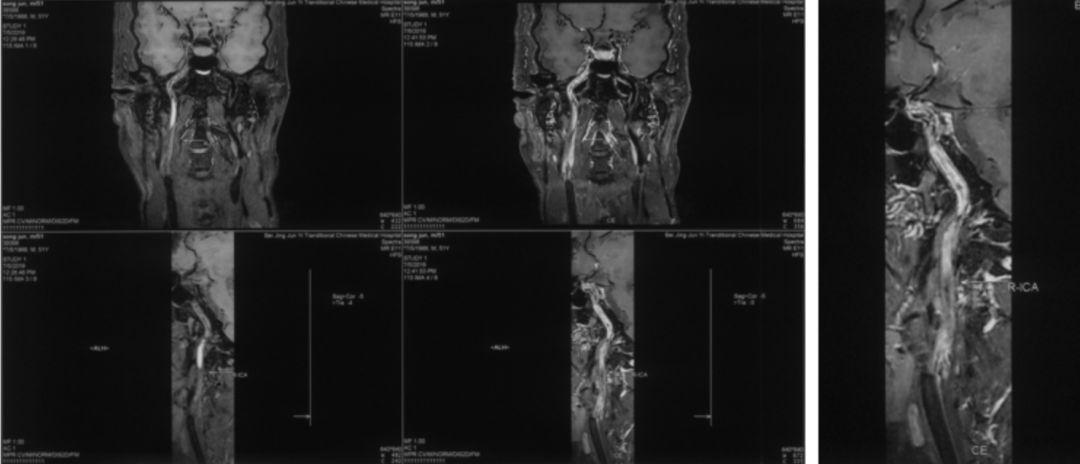

2019-07-05北京军颐中医医院高分辨核磁:

1.右侧颈内动脉夹层形成并血栓形成、管腔闭塞。

2.左侧颈内动脉眼段管腔中度狭窄,局部夹层不排除。

3.右侧大脑中动脉起始部管壁增厚,管腔重度狭窄(图3)。

图3